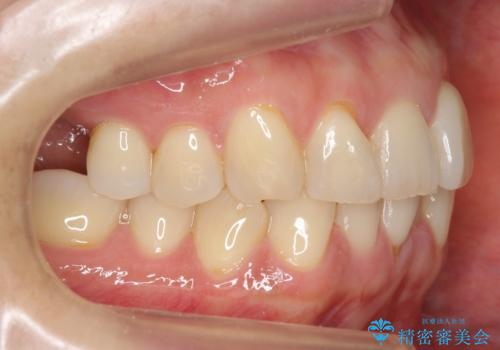

前歯が反対になっている マウスピース矯正+奥歯ブリッジ

- 前歯のがたつきを主訴に来院。

奥歯も少なく、左上奥歯はブリッジにすることになりました。

左下の前歯を中に入れるスペースを確保する目的で左下の奥歯を後ろ移動させました。

また、左下の小臼歯の捻転はマウスピースで治りにくいため、

事前にワイヤーによる部分矯正を行い、矯正用ミニスクリューを植立しています。